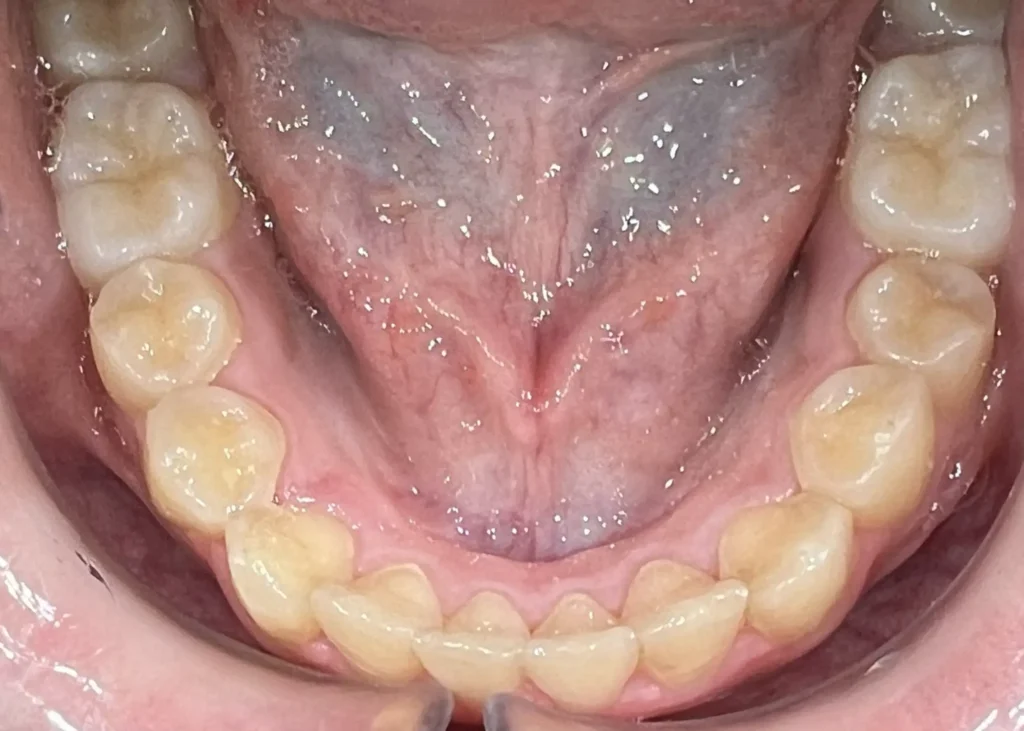

Casos clínicos de ortodoncia en CDPA